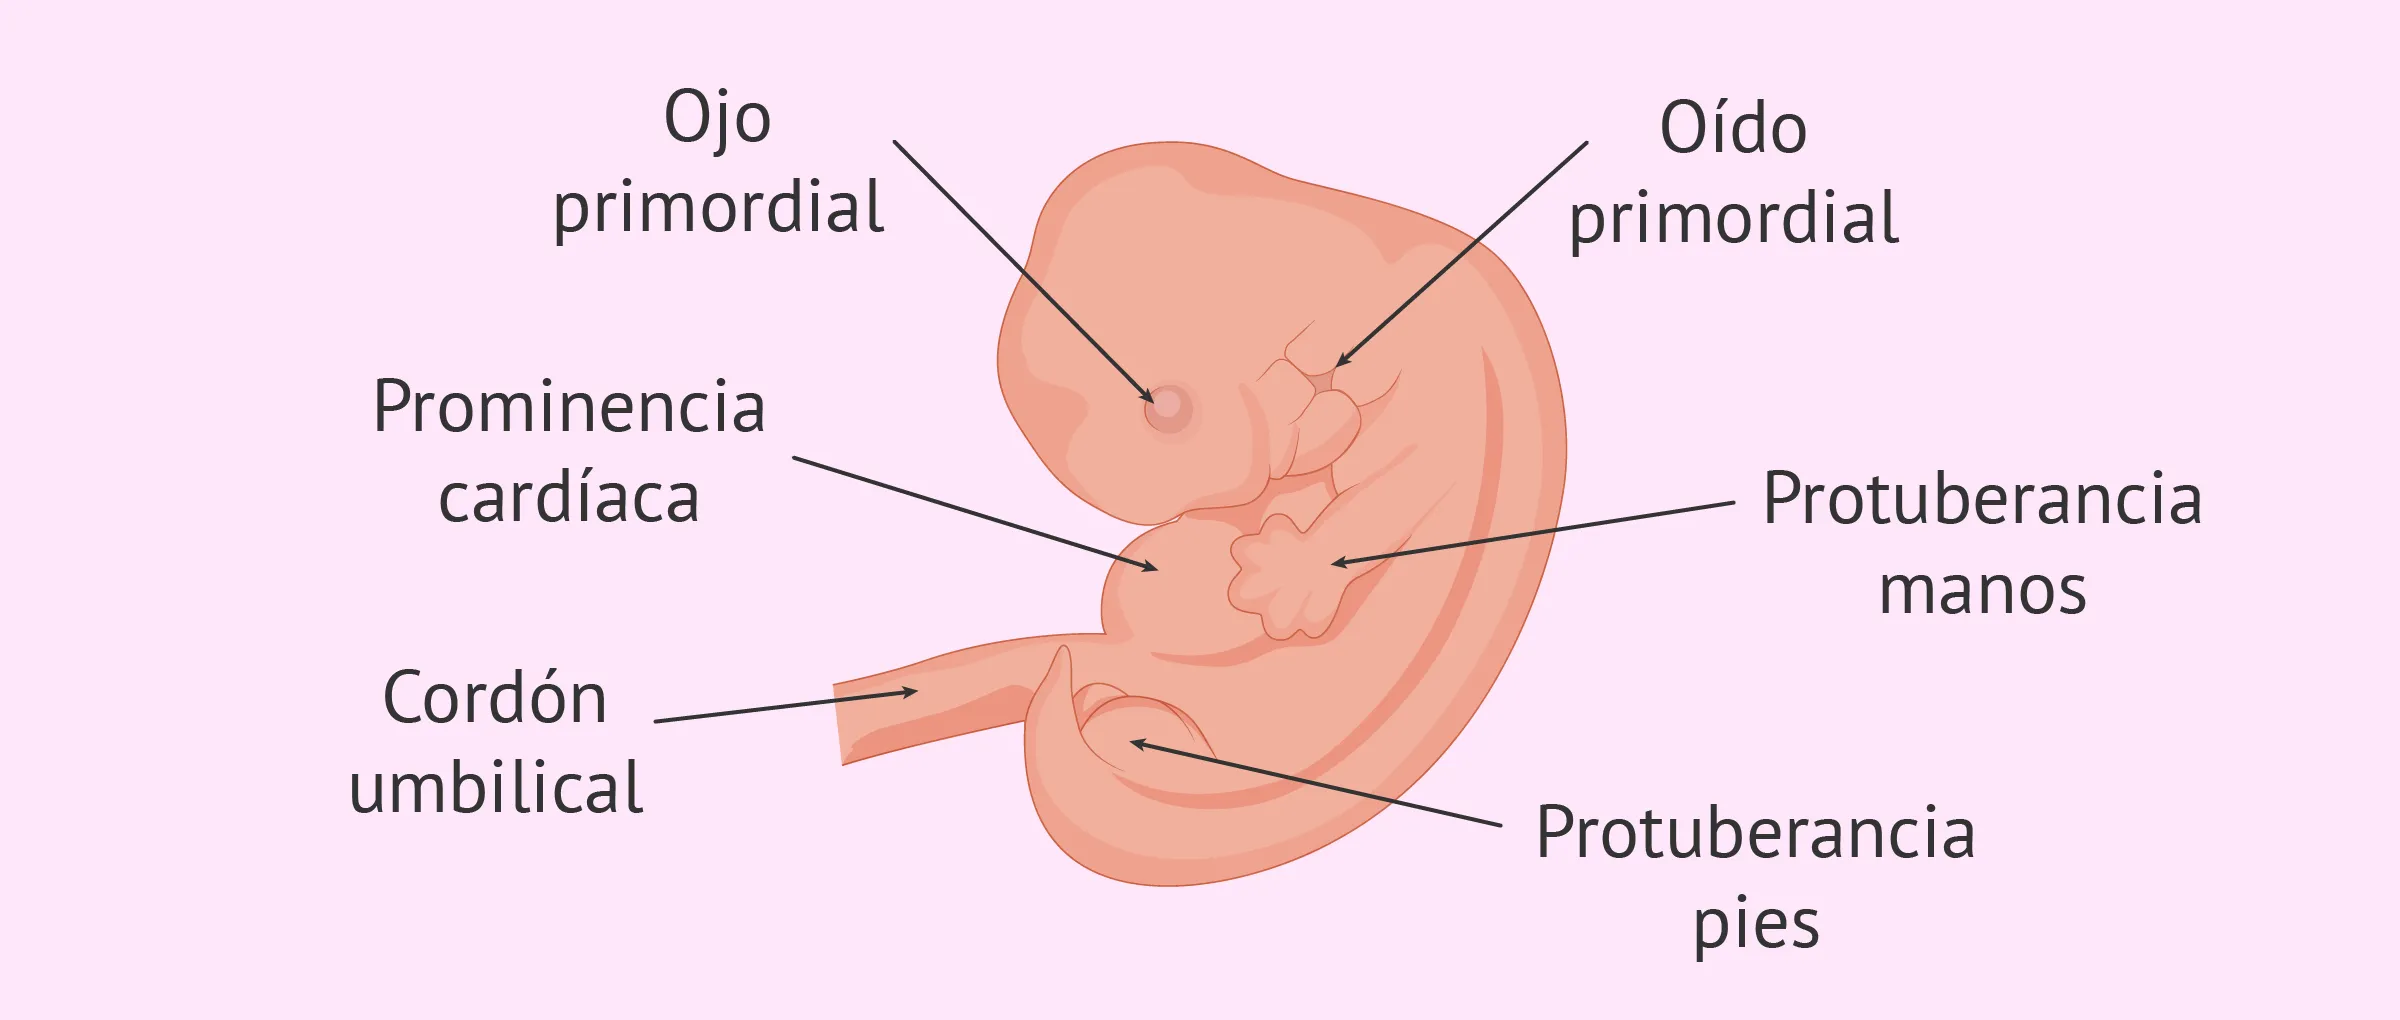

4 Semanas de embarazo: ¡Tu bebé es un embrión!

4 Semanas de embarazo: ¡Tu bebé es un embrión!

Semana 5 de embarazo: desarrollo del bebé y síntomas en la madre